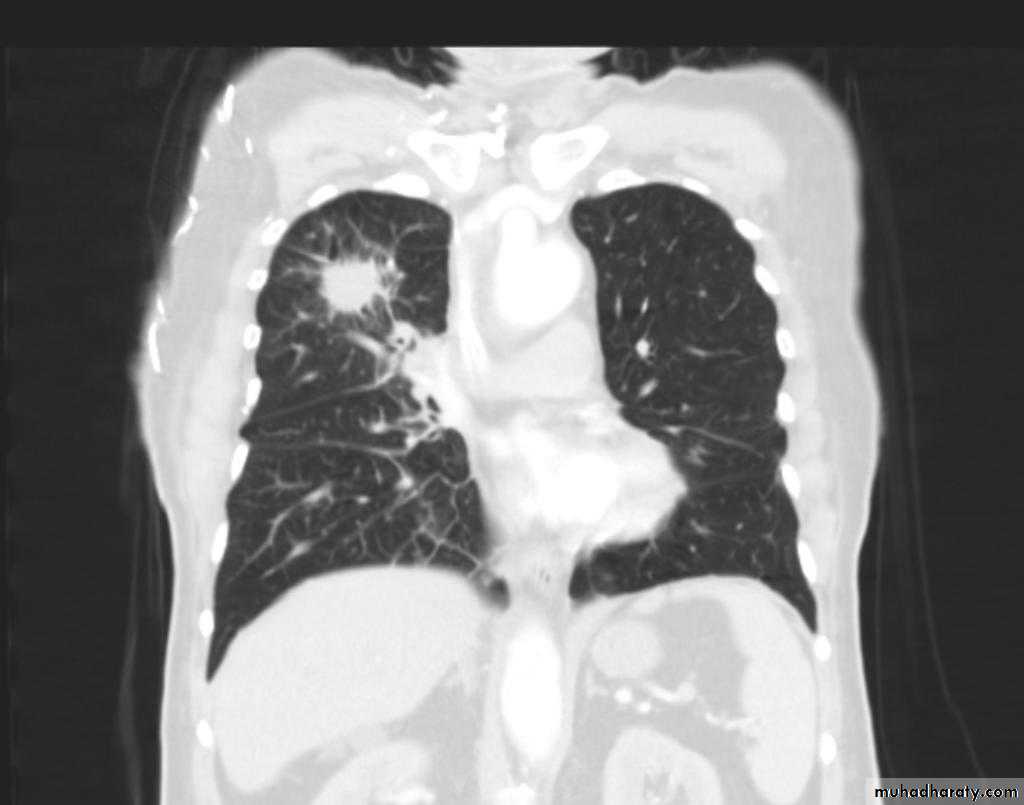

Secondary metastasis

74. secondary metastasis to the lung ( canon ball appearance )